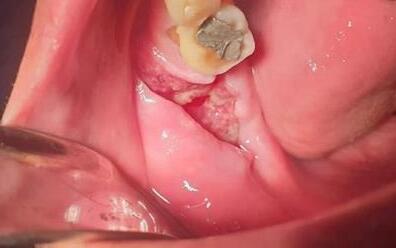

Presentación de caso clínico

Paciente masculino de 61 años de edad. Presenta lesión en la mucosa yugal derecha con forma de pápula de superficie rugosa adoptando una forma de coliflor de aproximadamente 2 cm, de consistencia fibrosa;de1añodeevolución.(Fig5).

Microscópicamente, las lesiones exhibenuna arquitectura exofíticay papilar con una base amplia. El epitelio puede ser moderadooacentuadamenteacantósicocon crestasreticularesbulbosas(Sato1997).En ocasiones, puede identificarse paraqueratosis con invaginaciones que rellenan las crestas entre las papilas (Eversole,2000).

5.

Condiloma acuminado, imagen clínica

Nota: Condiloma acuminado, imagen clínica (Foto cortesía de la Dra. Aurora Pérez Baché)

Setomabiopsiaescixional dondese observa epitelio escamoso estratificado con acantosis y escasa paraqueratosis, con prolongaciones epiteliales densas y elongadas, así como células coilociticas y crecimiento exofiticos (Fig 6). Después de entregar el diagnóstico de patología se recomendó seguimiento a largo plazo debido a que en algunas ocasiones puede habertransformaciónmaligna.